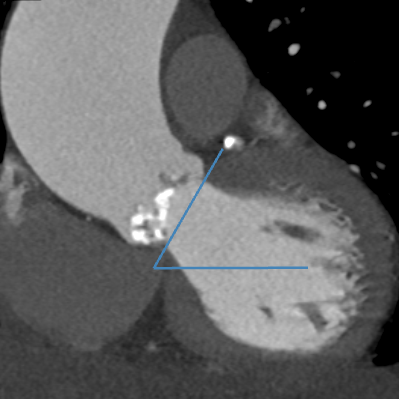

心脏CTA评估显示:Sievers 1型二叶式主动脉瓣,瓣叶明显增厚并重度钙化;瓣环周长82.7mm,瓣环面积534.9mm²;左冠状动脉开口高度12.6mm,右冠状动脉开口高度14.9mm;升主动脉最大直径60mm;横位心,瓣环角度60度。

血管入路评估:双侧股动脉细小且分叉高,最窄处不到5mm,不满足可用TAVR器械对于股动脉入路最小径线的要求。患者锁骨下动脉、颈动脉同样细小,无法作为替代入路。患者升主动脉瘤样扩张,经升主动脉入路风险极高。